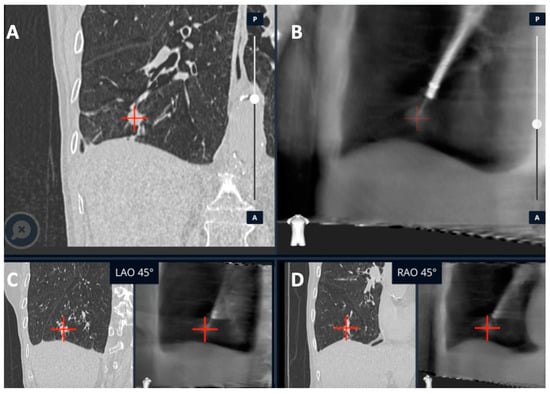

| Kalchiem-Dekel et al. [20] | Ion™ robotic platform with CIOS | Robotic platform for navigation with 3D multiplanar fluoroscopy for intra-procedural real-time guidance | 10 lesions | Tool in lesion: 90%. Tool correction in 30% lesions with real-time imaging. DY not reported | - |

| Reisenauer et al. [11] | Ion™ robotic platform with CIOS | Robotic platform for navigation with 3D multiplanar fluoroscopy for intra-procedural real-time guidance | 30 lesions | DYi: 93%. Average divergence: 10 mm in upper lobe 20 mm in lower lobe | No adverse events |